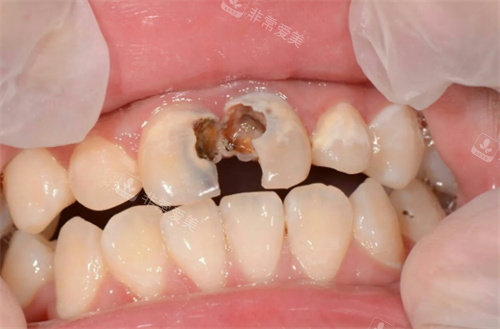

龋坏牙治疗

牙齿龋坏

牙齿龋坏钻洞实拍